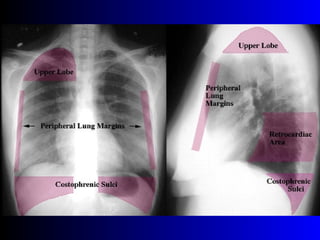

Este documento describe la técnica para realizar una telerradiografía de tórax normal e identifica las estructuras visibles en la imagen, incluyendo los huesos, vasos sanguíneos, grasa, tejido subcutáneo, pulmones y mediastino. Explica que es importante centrar la imagen en los ápices pulmonares, senos costodiafragmáticos e inspiración profunda para una visión clara de las estructuras.